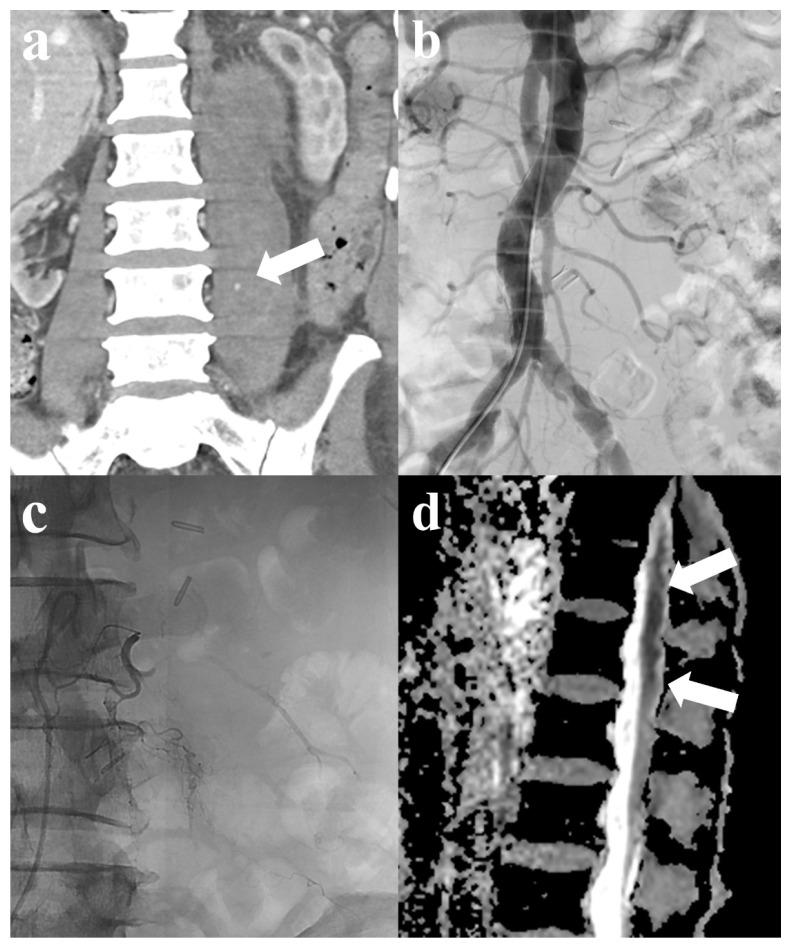

经导管动脉栓塞术治疗创伤性或自发性腰大肌及腹膜后出血患者的临床疗效与安全性

Clinical Outcomes and Safety of Transcatheter Arterial Embolization in Patients with Traumatic or Spontaneous Psoas and Retroperitoneal Hemorrhage.

We aimed to assess the effectiveness and safety of transcatheter arterial embolization (TAE) in the management of spontaneous or traumatic psoas and/or retroperitoneal hemorrhage. This single-center retrospective study enrolled 36 patients who underwent TAE for the treatment of psoas and/or retroperitoneal hemorrhage between May 2016 and February 2024. The patients' mean age was 61.3 years. The spontaneous group (SG, 47.1%) showed higher rates of anticoagulation therapy use compared with the trauma group (TG, 15.8%) ( = 0.042). The TG (94.7%) demonstrated higher survival rates compared with the SG (64.7%; = 0.023). Clinical failure was significantly associated with the liver cirrhosis ( = 0.001), prothrombin time ( = 0.004), and international normalized ratio ( = 0.007) in SG and pRBC transfusion ( = 0.008) in TG. Liver cirrhosis (OR (95% CI): 55.055 (2.439-1242.650), = 0.012) was the only identified independent risk factor for primary clinical failure in the multivariate logistic regression analysis. TAE was a safe and effective treatment for psoas and/or retroperitoneal hemorrhage, regardless of the cause of bleeding. However, liver cirrhosis or the need for massive transfusion due to hemorrhage increased the risk of clinical failure and mortality, necessitating aggressive monitoring and treatment.

摘要

我们旨在评估经导管动脉栓塞术(TAE)治疗自发性或创伤性腰大肌和/或腹膜后出血的有效性和安全性。这项单中心回顾性研究纳入了2016年5月至2024年2月期间接受TAE治疗腰大肌和/或腹膜后出血的36例患者。患者的平均年龄为61.3岁。与创伤组(TG,15.8%)相比,自发性组(SG,47.1%)抗凝治疗的使用率更高(P = 0.042)。与SG组(64.7%;P = 0.023)相比,TG组(94.7%)的生存率更高。临床失败与SG组的肝硬化(P = 0.001)、凝血酶原时间(P = 0.004)、国际标准化比值(P = 0.007)以及TG组的红细胞悬液输注(P = 0.008)显著相关。在多因素逻辑回归分析中,肝硬化(OR(95%CI):55.055(2.439 - 1242.650),P = 0.012)是唯一确定的原发性临床失败的独立危险因素。无论出血原因如何,TAE都是治疗腰大肌和/或腹膜后出血的安全有效方法。然而,肝硬化或因出血需要大量输血会增加临床失败和死亡的风险,需要积极监测和治疗。